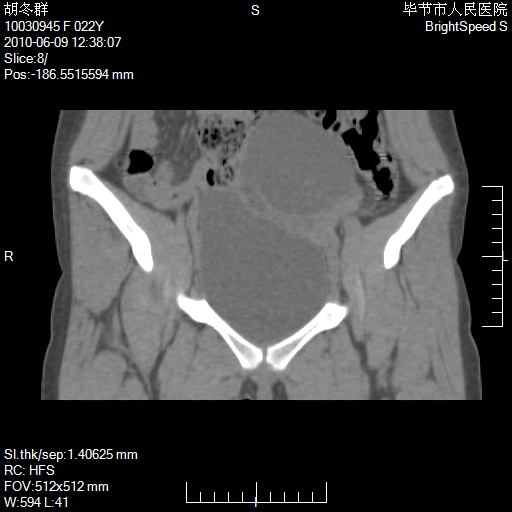

患者23岁,发现腹部包块3月。

左侧卵巢囊腺瘤或囊腺癌

盆腔内囊性占位性病变;考虑左侧卵巢囊腺瘤。

有分隔、壁薄,支持考虑左侧卵巢囊腺瘤。

左侧卵巢浆液性囊腺瘤。

支持考虑左侧卵巢囊腺瘤;宫腔积液。

有分隔、壁薄,支持考虑左侧卵巢囊腺瘤。排尿后,膀胱缩小,由于重力作用,肿块下移就到了膀胱位置,很好理解。